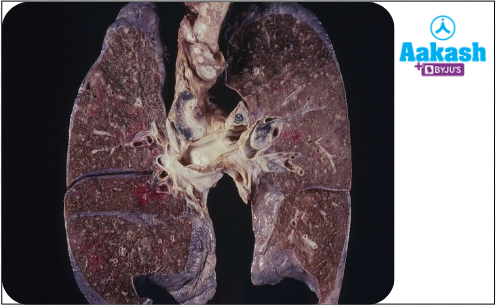

Lung tissue is lost in pulmonary tuberculosis and replaced with fibrous connective tissue Tuberculosis is a very contagious disease. This means that the bacterium can quickly spread from one sick person to the healthy person easily. It primarily affects the lungs, but if left untreated, it might spread to different parts of the body. A chest X-ray along with a blood test is performed normally for diagnosis.

Fig: Condition of lungs in pulmonary tuberculosis